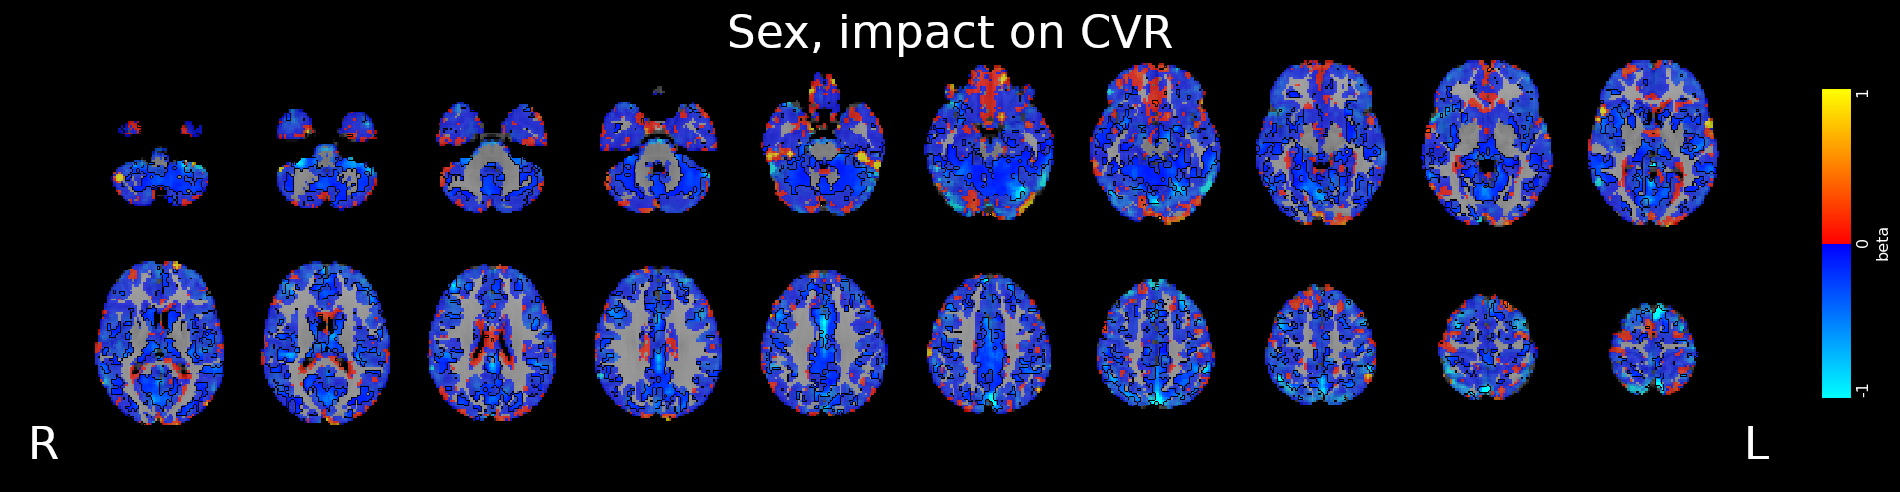

Results: sex

- Females show higher CVR than males in most of the GM

- Previous studies report CVR higher in females¹, in males², or no differences between the two³

- A possible cause of this difference might be related to hormonal changes during the menstrual cycle

1. Kastrup et al. 1997, 1998 (Stroke), Tallon et al. 2020 (Exp. Psychol.); 2. Kassner et al. 2010 (J. Magn. Reson. Imaging)

3. Chen et al. 2021 (Int. J. Imaging Syst. Technol.), Jiménez Caballero et al. 2006 (Rev Neurol)

Results: sex

Effect of Sex

Only sex had a significant effect on RSF

Effect on CVR

- Stationary blood pressure changes, expressed as MAP and PP, as well as sex, impact regional CVR estimation differently across sessions and subjects